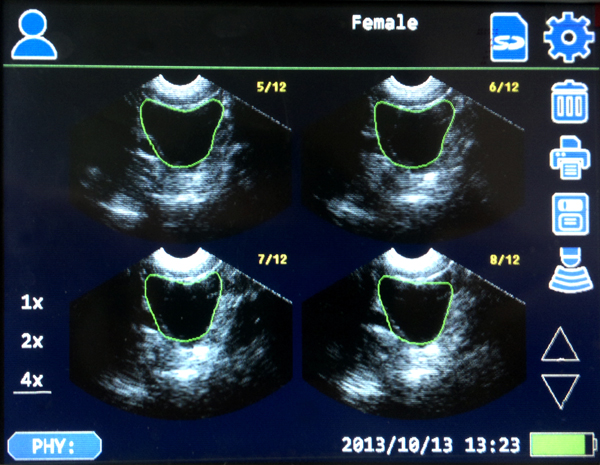

Avantages du produit - Algorithme plus avancée, la technologie de reconnaissance paroi de la vessie plus puissante , la technologie plus précise des contours, une plus grande précision de la sonde rend résultats d'analyse plus précis. - Nouvel algorithme , les résultats des mesures ne sont pas soumis à la forme et taille de la vessie. Pas besoin de sélectionner le sexe, groupe d'âge et le pas besoin d'examiner des cas particuliers tels que l'effet de l'hystérectomie sur les résultats de mesure. Bonne compatibilité des différents vessies, aucune erreur importante lorsque la mesure de petites vessies ou vessies de forme spéciale , facile à utiliser - Taux de reconnaissance élevé pour la paroi de la vessie avec de l'air , la quantité précise du volume d'urine , même quand la vessie n'est pas complètement remplie. - Avec les fonctions manuelles de contour, lorsque Contour automatique est vraiment difficile , cela peut être contourné manuellement via l'écran tactile, afin de s'assurer que les résultats précis peuvent être obtenus même si la frontière de la vessie est anormal. - L'imagerie en temps réel pendant le processus d'analyse, de surveillance en temps réel de l'insertion du cathéter afin de mieux prévenir la douleur causée par l'insertion inapproprié. -10ml ~ 2000ml grande plage de mesure - La sonde utilise un nouveau moteur pas à pas en trois dimensions, peut maintenir durablement la numérisation de haute précision, étalonnage périodique n'est pas nécessaire. -Paramètres identifiables à l'intérieur de la sonde, la sonde peut être rapidement remplacé sans l'étalonnage secondaire. - Built-in 24Wh grande capacité de la batterie , le temps de travail continu > 4 heures, la batterie peut être rapidement remplacé . - Le fonctionnement de l'écran tactile , les menus simples, faciles et rapides à utiliser . - Compact et léger, facile à transporter.

Application: Scanner de la vessie est utilisée pour visualiser, suivre et mesurer de manière non invasive le volume d'urine dans la vessie, afin de déterminer si d'uriner est nécessaire et le débit urinaire et pour éviter une insertion inappropriée du cathéter dans la vessie. Scanner de la vessie est largement utilisé en urologie, la réadaptation, la chirurgie, salle d'opération et les soins de santé à domicile. Avantages de la numérisation de la vessie • Calcule le volume de la vessie et le résidu postmictionnel • Évite les sondages non nécessaires et l'inconfort du patient • Diminue les risques d’infection des voies urinaires • Surveiller la vessie non invasif pour éviter la rétention urinaire • Surveiller la récupération post-opératoire • Réduit les coûts hospitaliers (jetables) • Favorise l'efficacité du personnel et nécessite peu de formation.

Manual Contour functions